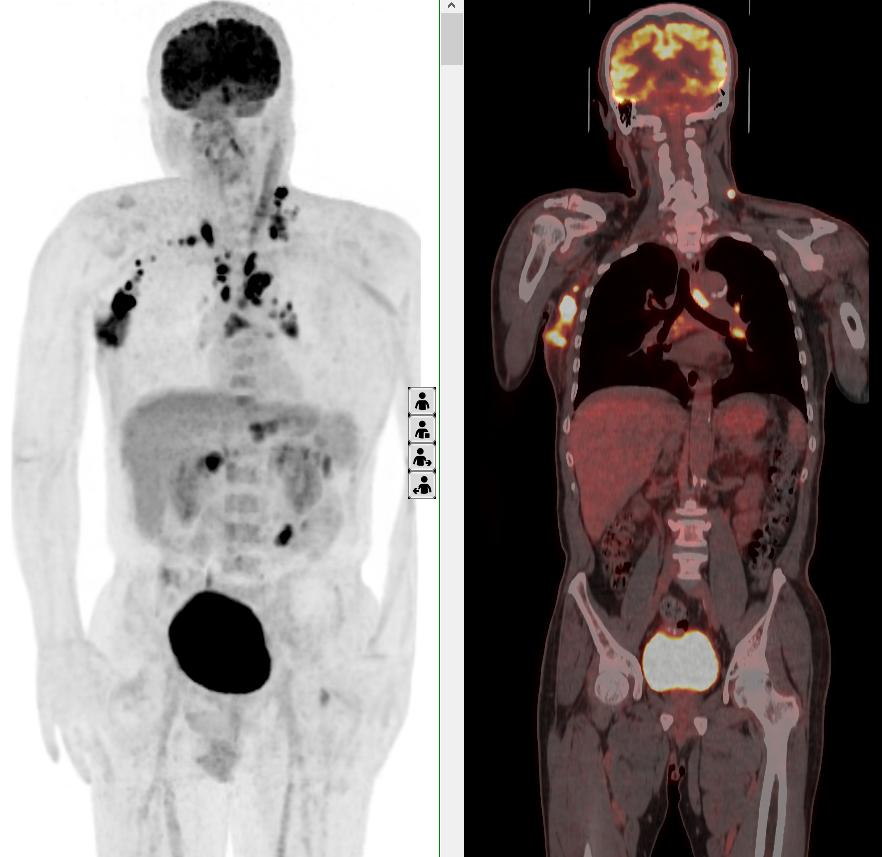

頸胸部多處代謝異常病灶

完善PET/CT檢查示:右側腋窩、雙側中下頸部、縱隔、雙側肺門多發(fā)MT,建議淋巴結活檢。后患者行右腋窩淋巴結切除活檢術,經北京大學第三醫(yī)院病理科會診示:右腋窩淋巴結惡性腫瘤,呈淋巴竇內生長模式,瘤細胞呈上皮樣,異型性明顯,伴中性粒細胞浸潤。結合病史及免疫組化,考慮為SMARCA4(BRG1)缺失的胸部腫瘤,伴神經內分泌標記表達。

本例為罕見病理類型的腫瘤,影像學表現無明顯特異性,診斷困難。強化CT和穿刺病理已基本明確為惡性腫瘤,行PET/CT檢查一是為了全身檢查,完善分期,二是根據PET代謝情況指導進行生物靶區(qū)活檢,進一步明確病理診斷。最終,PET/CT除縱隔病變外發(fā)現更多頸胸部淋巴結代謝異常,綜合考慮后對腋窩淋巴結進行切除活檢,最終得到病理證實。